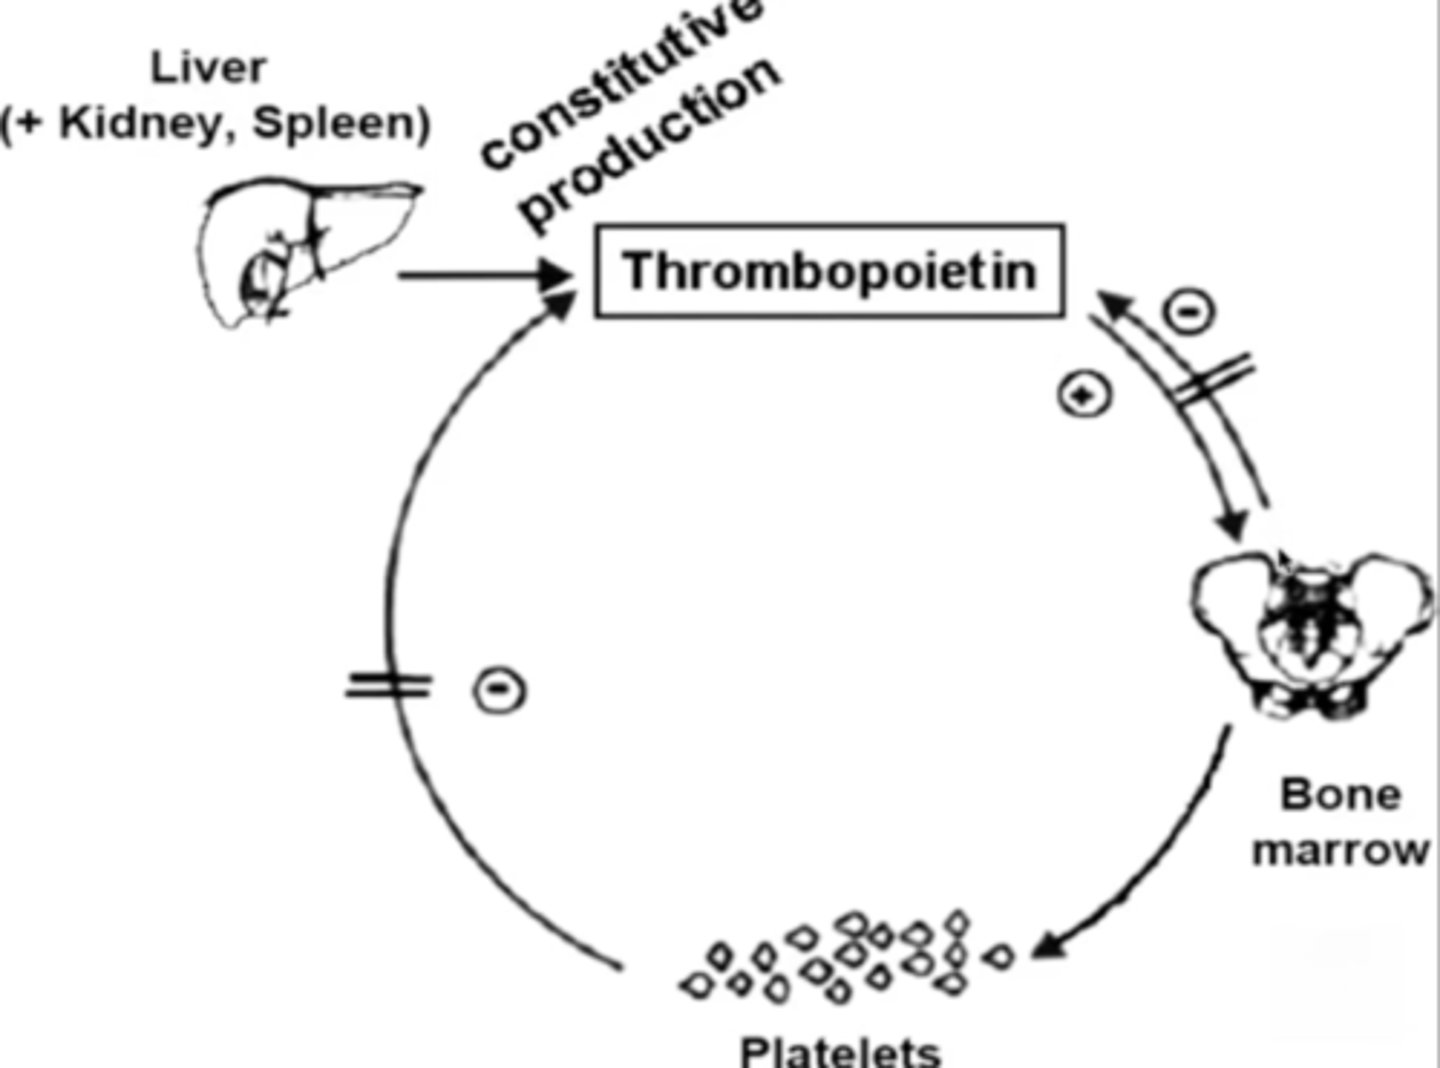

TPO

Thrombopoietin; stimulates platelet production